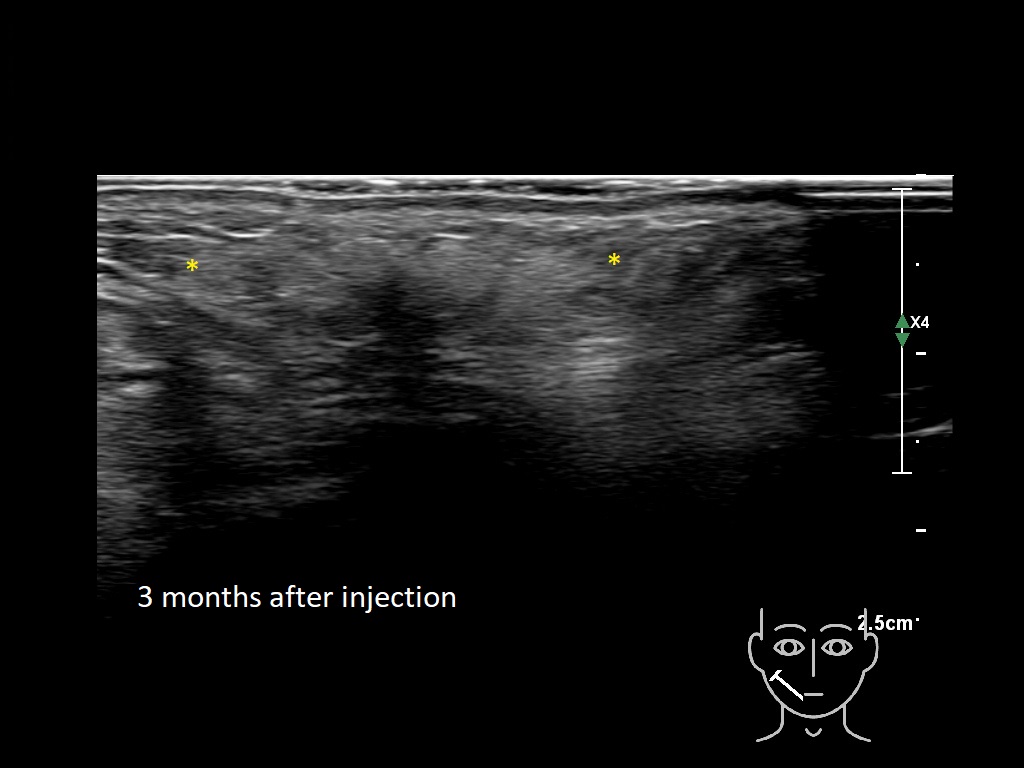

Draw in the image on the right where the fillers are located. To check if your answer is correct, please click on the secondary image.

Draw in the second image below where the fillers are located. To check if your answer is correct, swipe the first image to the right.